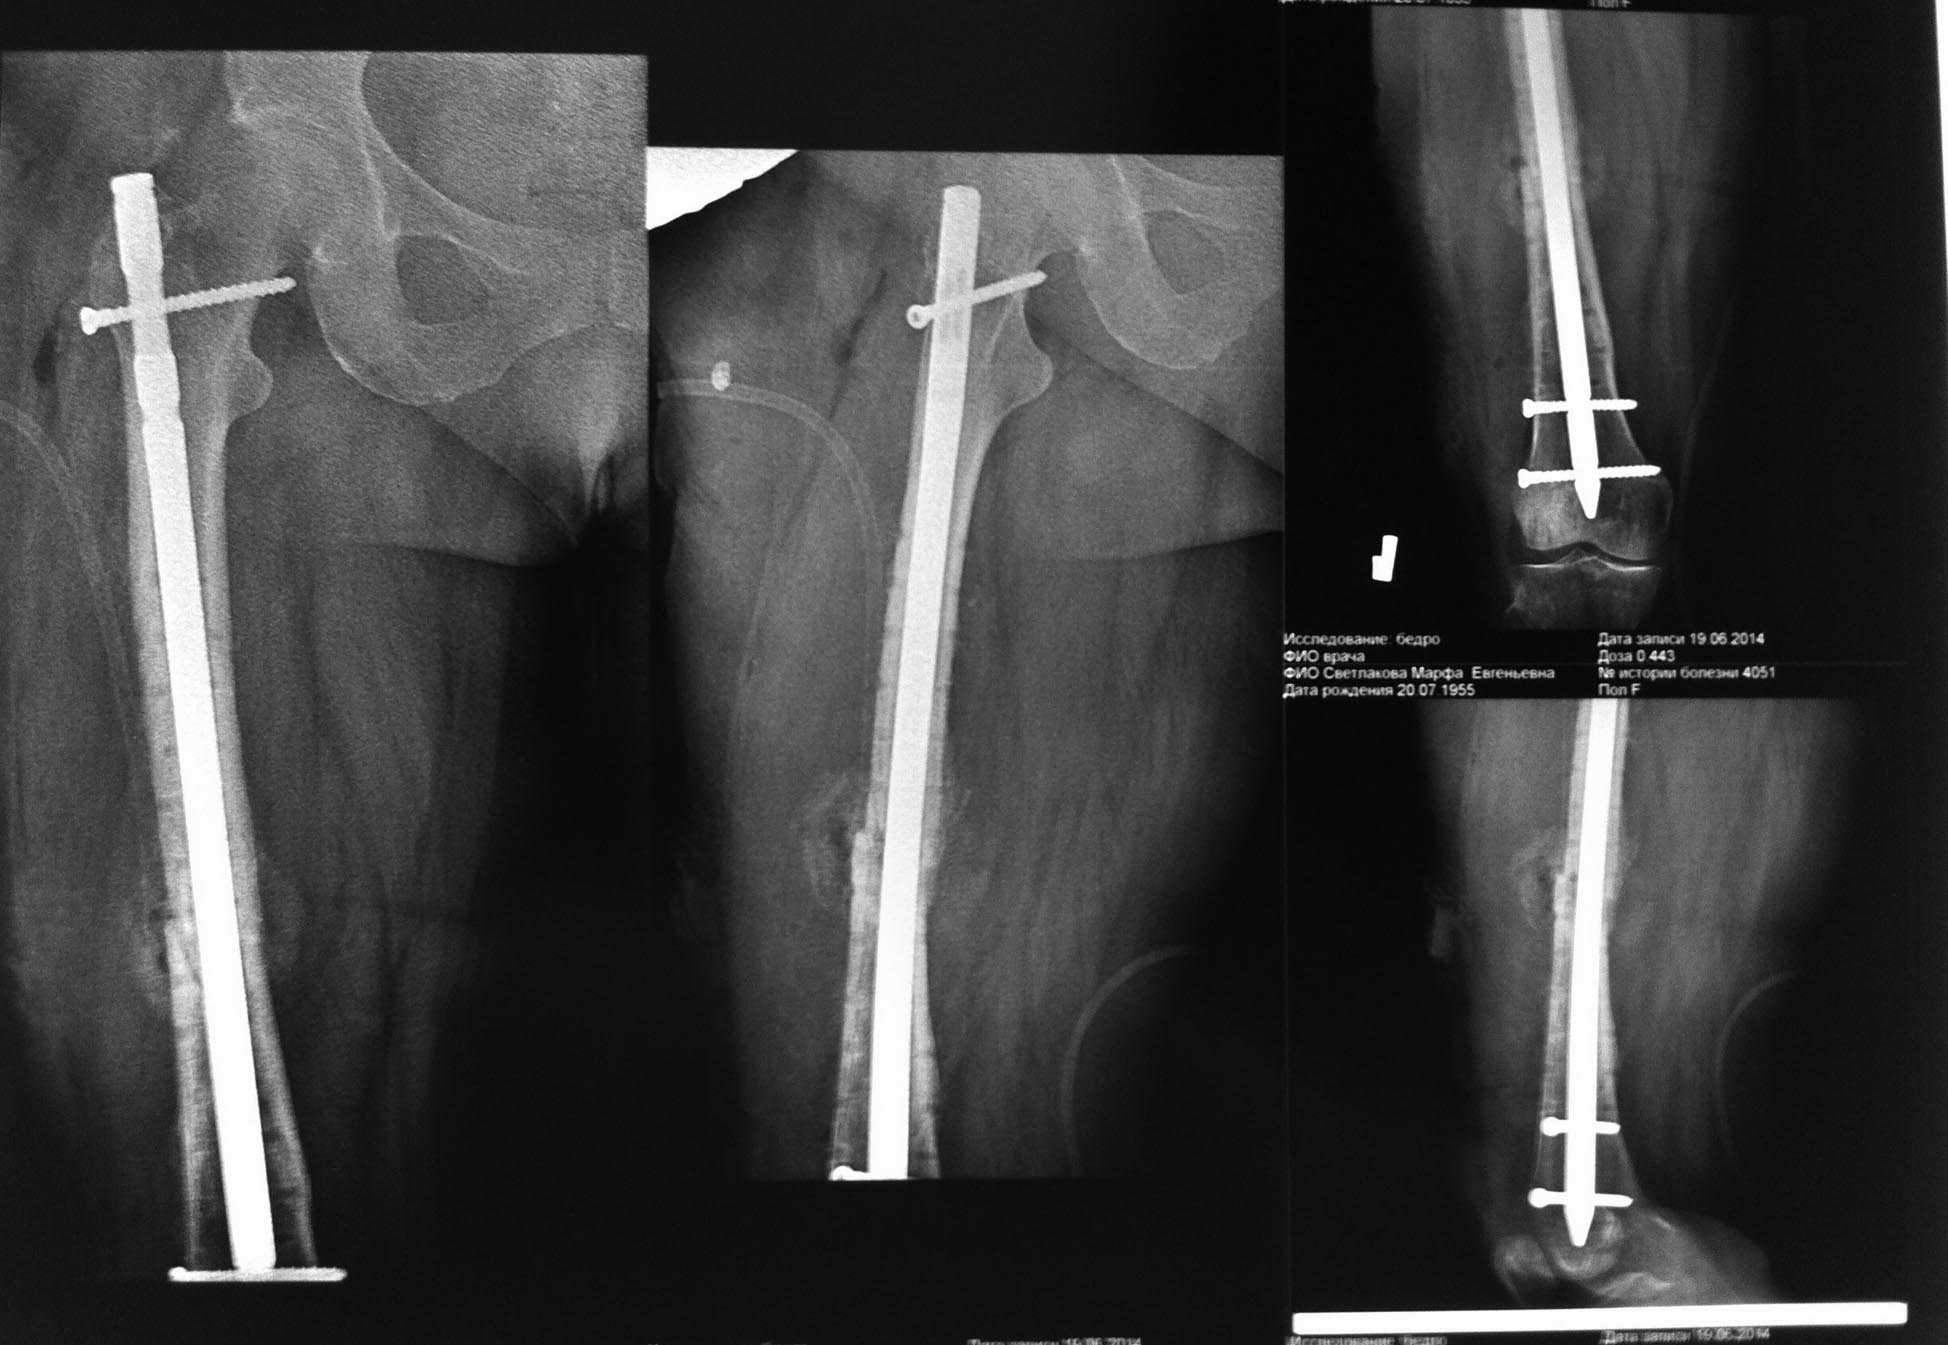

Удалить пластину и выполнить интрамедуллярный остеосинтез (возможно с рассверливанием канала). Винты ломались из-за слишком высокой концентрической нагрузки в зоне перелома засчет большого количества винтов. Если уже ситуация только с пластиной, я бы её чуть поднял, и уменьшил бы количество винтов, но гвоздь всё- таки предпочтительней.

Это не повторный перелом, а несостоятельная фиксация. А почему диафизарный перелом бедра синтезирован пластиной, а не закрыто гвоздем? Ответ на этот вопрос нужен, чтобы думать над тем, что делать дальше.

Уважаемый Alexey данный перелом по классификации АО 32В3 - относится к сложным . О достижении абсолютной стабильности нужно забыть! Шинирование с достижением относительной стабильности, выбором импланта от вертельной зоны до мыщелков поможет справиться с данной ситуацией.

Уважаемые коллеги, к сожалению, первичных снимков у нас нет. Почему наши друзья сделали именно так, а не иначе, остается только гадать. Согласен, что выполненный МОС бедра не адекватен для типа перелома, но смущает, что перелом винтов произошел практически без нагрузки. Бывает МОС и похуже, но винты не ломаются при этом. В отделении планируется АВФ бедра, хотя рассматривается вариант и интрамедуллярного синтеза (????).

Для этого перелома пластина абсолютно не подходит, т.к. по внутренней поверхности, если я хорошо увидел имеется оскольчатый перелом, таким образом кость не "защищает" пластину, а наоборот, вызывает сильную нагрузку на варус. В таких случаях очень часто наступает дебриколяж (перелом пластины), в Вашем случае перелом винтов. Вы и сами видите, что после перелома фрагменты приняли варусное положение, сместившись в зону дефекта, фрагменты к этому стремились, они этого добились. Кроме этого пластина слишком короткая, нужно было накладывать практически на весь диафиз. Обязательно нужно было делать костную пластику по внутренней поверхности бедра в месте оскольчатого перелома и производить межфрагментарную компрессию. Но стоило ли это таких усилий? Поэтому, только ЗИМО.

Спасибо коллеги за присланные советы. По результатам дальнейшего лечения отпишусь. Попробуем выкрутить винты и выполнить ЗИМО.

Однозначно удалить пластину, винты. Рассверлить канал и относительная стабильность на штифте с блокированием. Был аналогичный случай, оперировал спустя 3 месяца, так же, коллапс импланта, варус.

Удалили пластину, рассверлили канал, компрессия и заблокировали сразу в динамику. На 3 сутки ходьба с костылями с 50% опорой на ногу, ЛФК. Пациентка результатом довольна.